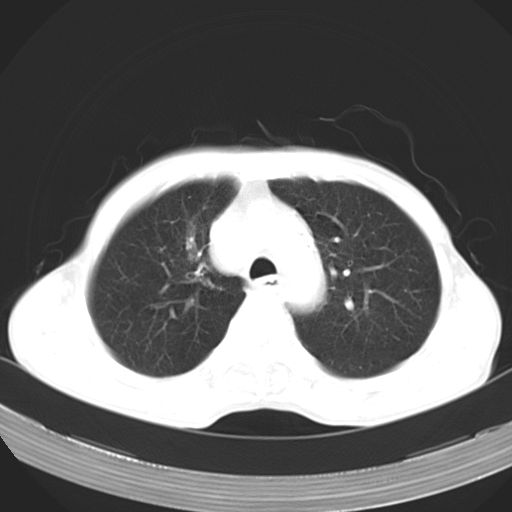

以下是引用苯小孩在2007-5-24 12:47:00的发言:[br]右侧肺门处不均匀密度软组织块影,远端肺组织见斑片模糊影,纵隔内淋巴结明显肿大,边界不清.<纵隔窗第12层面支气管内似见软组织结节>[br]考虑:1、右侧中央性肺癌并阻塞性肺炎并纵隔淋巴结转移可能性大.建议强化或纤支镜进一步检查.[br]2、隆突下淋巴结肿大/食道病变?请做鉴别检查.

以下是引用zhangzhongshou在2007-5-24 12:55:00的发言:[br]1、右肺中叶中心型肺癌并右肺门、隆突下、纵隔淋巴结转移。右肺中叶阻塞性肺炎。

以下是引用jw-830在2007-5-24 15:24:00的发言:[br][br] [br] 考虑右肺中央型肺癌并阻塞性炎症,右肺门及纵隔淋巴结转移。 [br] [br][br]